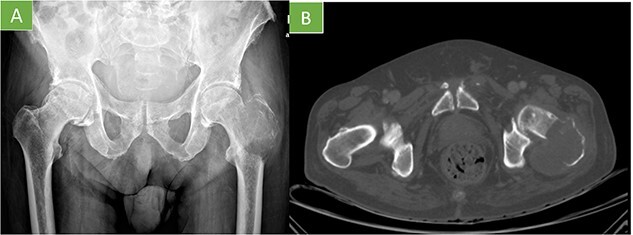

Radiografía / TC

Lesión lítica agresiva con destrucción cortical y posible componente de partes blandas. No es patognomónico.